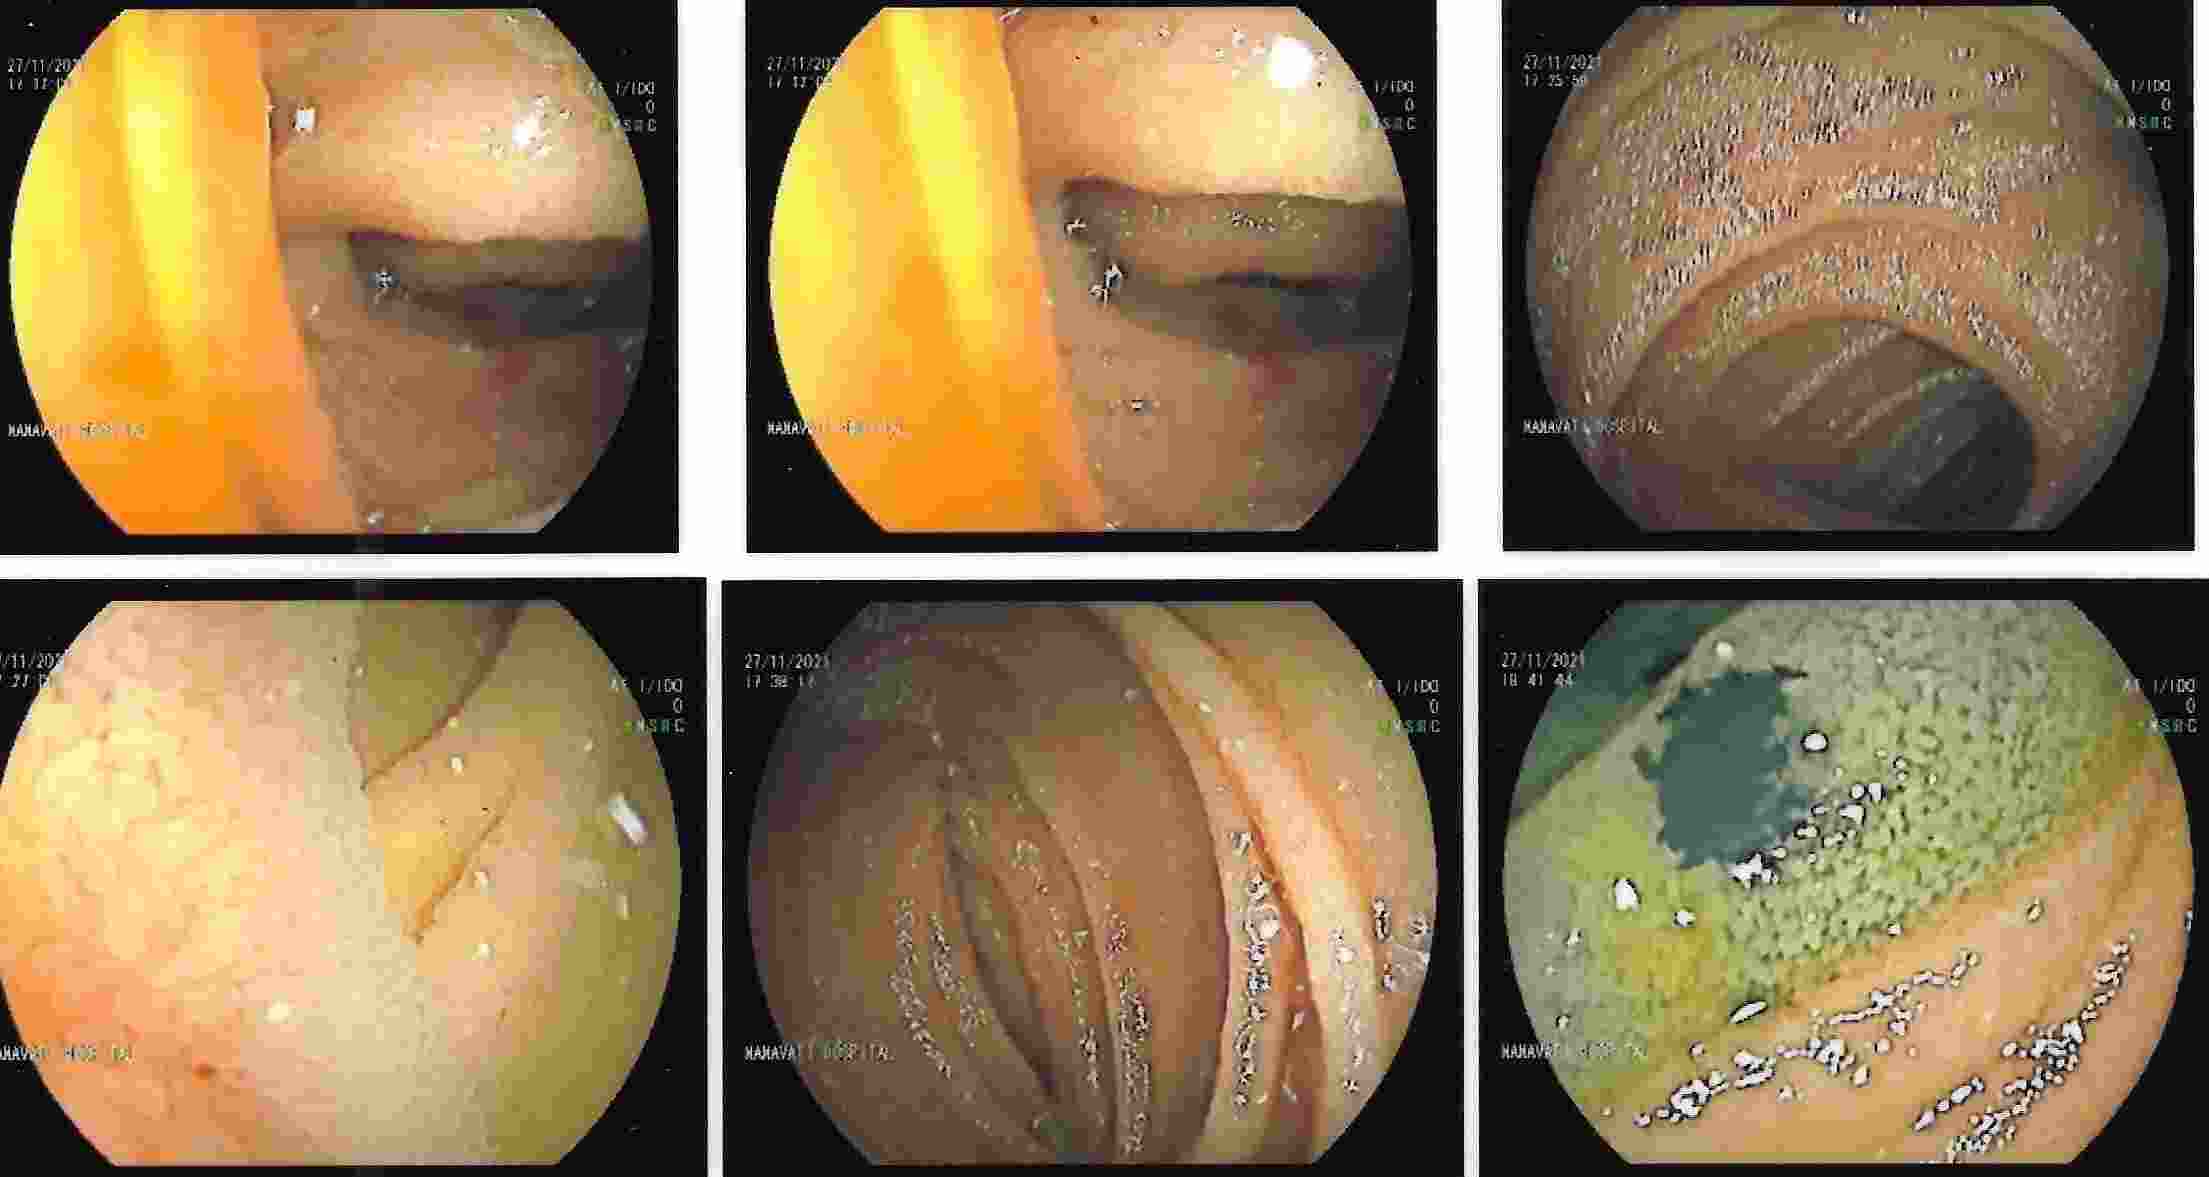

COLONOSCOPY

Colonoscopy is a procedure where the doctor can examine the lowermost part of the digestive tract

by a flexible instrument called as Colonoscope. Common indications for Colonoscopy are

1. Constipation.

2. Loose motions.

3. Pain in lower abdomen.

4. Excessive gas from below.

5. Burning or pain in anal region.

6. Altered bowel habits.

7. Frank blood in the stool, occult blood in the stool or anaemia.

These conditions are seen more often in elderly people where Colonoscopy is essential for making an early diagnosis of cancer of the colon.

Colonoscopy is advocated for first blood relations of the patient who has got cancer of the colon.

Common mistake is to attribute blood in the stool for piles or fissure and get wrongly treated for a long time.

The correct diagnosis of cancer of the colon or rectum if made in time can offer a curative treatment.

Major bleeding in the stool in elderly people is commonly due to diverticulitis of colon.

This is a condition where there are balloon like projections arising from colonic mucosa and

which bleed due to rupture of a blood vessel. Colonic polyps is also an important condition to diagnose because

polyps have potential of becoming cancerous in future. Removal of polyp by polypectomy without

open surgery can offer cure in the early stage of cancer. A proper follow-up can keep the patient free from cancer.

Altered bowel habits, watery or semisolid stools, gripping pain in abdomen, mucus and blood in the stool,

incomplete evacuation can all be due to a condition called as colitis. Colitis has got different causes

like ulcerative colitis, Crohn’s disease, infections, tuberculosis, amoebic colitis, bacillary dysentery and many more.

Corrcet diagnosis by Colonoscopy will allow patients to be treated properly.

IBD - Ulcerative Colitis

IBD - Crohn's Disease

Ulcerative Colitis

Ulcerative Colitis

Crohn's Disease